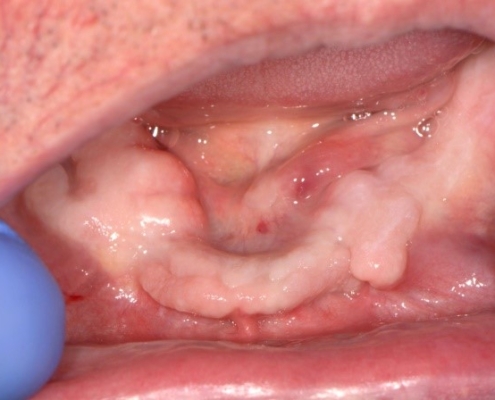

Mobilno-protetska terapija pacijenata s nezavršenim rastom i razvojem